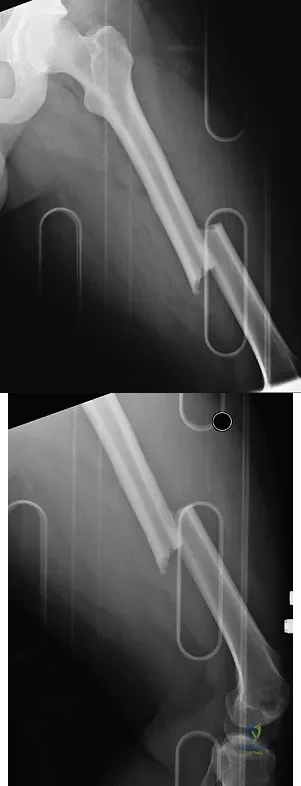

A 24-year-old man was thrown from a car and is seen in the emergency department with a Glasgow Coma Scale (GCS) score of 8. A CT scan of the head shows no significant bleeding. The patient is hemodynamically stable. The left femur has the closed injury shown on the radiographs in Figures 53a and 53b. What is the best treatment for this patient?

Explanation

Treatment of patients with a closed head injury and a femoral fracture remains controversial but recent data suggest that intramedullary nails done acutely with avoidance of intraoperative hypotension did not compromise the outcome related to the head injury. This was especially true for high-level GCS scores. A GCS score of lower than 8 and intraoperative hypotension have been associated with worsening outcomes following acute intramedullary nailing of the femur. Skin traction and distal femur skeletal traction in a young adult man with a femoral fracture is not well tolerated secondary to spasm and pain. External fixation is an option but an unnecessary step in the treatment of this patient. Ventriculostomy is not necessary in stable patients with no significant bleeding on a CT scan of the head. Starr AJ, Hunt JL, Chason DP, et al: Treatment of femur fracture with associated head injury. J Orthop Trauma 1998;12:38-45. Nau T, Kutscha-Lissberg F, Muellner T, et al: Effects of a femoral shaft fracture on multiply injured patients with a head injury. World J Surg 2003;27:365-369. McKee MD, Schemitsch EH, Vincent LO, et al: The effect of a femoral fracture on concomitant closed head injury in patients with multiple injuries. J Trauma 1997;42:1041-1045.